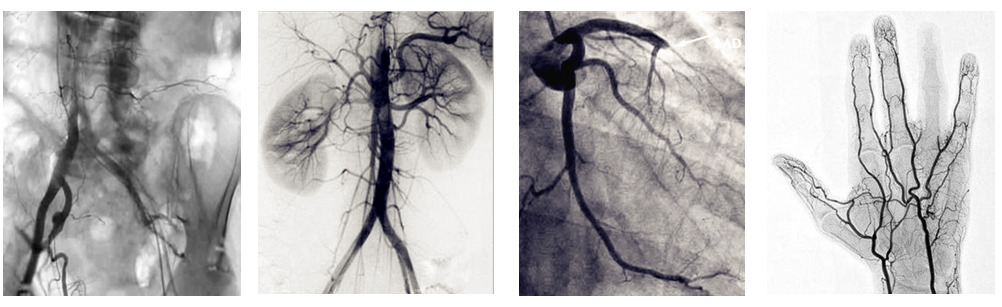

介入c臂機可以把不需要的組織影像刪除掉,只保留血管影像。圖像清晰,分辨率高,對觀察血管病變,血管狹窄的定位測量,診斷及介入治療提供了真實的立體圖像,還具有多種工作模式,靈活方便,滿足各種臨床需要,為各種介入治療提供了必備條件。

PLX7100A移動式介入c臂機,體積小,劑量低,圖像清晰,是廣大基層醫院介入腫瘤科以及三甲醫院專科介入(如肝膽外科、ERCP室、婦科)使用的理想設備。